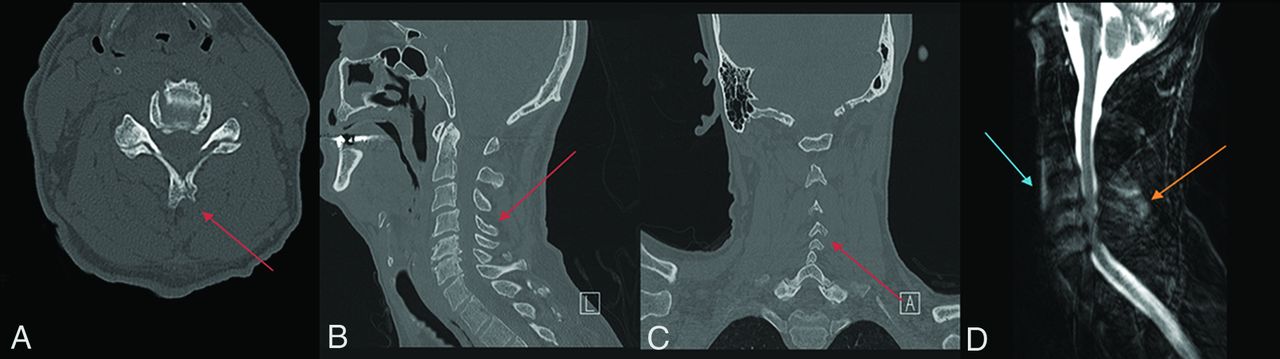

Fracture-positive, radiologist false-negative, CNN false-negative case example. Axial (A), sagittal (B), and coronal (C) cervical spine CT images, and sagittal fat-saturated T2-weighted cervical spine MR image (D) demonstrate a minimally displaced C4 spinous process fracture. Red arrows demarcate fracture lines, the blue arrow demarcates prevertebral edema, and the orange arrow demarcates interspinous and supraspinous ligamentous injury. This case example illustrates a subtle fracture missed by both the radiologist and CNN that was identified in retrospect with the help of MR imaging because of the presence of secondary signs, such a prevertebral edema and ligamentous injury.